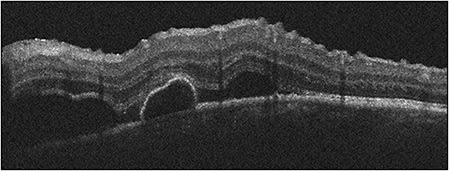

The conglomerate of white dot syndromes includes inflammatory disorders of the outer retina, retinal pigment epithelium, and choroid and is comprised of multiple evanescent white dot syndrome, acute posterior multifocal placoid pigment epitheliopathy (APMPPE), multifocal choroiditis (MFC) with or without panuveitis, punctate inner choroiditis (PIC) and acute zonal occult outer retinopathy. White dot syndromes generally present similarly in adults and children. Multiple evanescent white dot syndrome produces a granular macular appearance with tiny subretinal white or yellow lesions, while APMPPE typically has larger lesions that block early on fluorescein angiography. As with adults, neurologic symptoms can accompany the diagnosis of APMPPE and a neurological review of system is essential. MFC and PIC both have distinct subretinal lesions; MFC has vitritis and PIC does not. Acute zonal occult outer retinopathy tends to impact young women with an enlarged blind spot and ellipsoid zone changes (Figure 3). Autoflouresence can reveal zonal areas of hyperautofluorescence and hypoautoflouresnce. Patients should be monitored for the development of choroidal neovascular membranes in any of these etiologies.

Like SO, VKH is a T-cell mediated response to retinal and uveal antigens. It occurs more often in Asians, Hispanics, and Native Americans. Systemic findings include central nervous system changes, including aseptic meningitis, and cutaneous manifestations, such as vitiligo and poliosis. Pediatric cases comprise up to 15% of VKH cases and often the disease is more aggressive in children than in adults (Figure 2).16